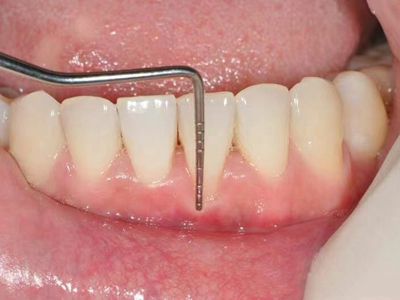

牙龈退缩牙龈萎缩露出牙根图

牙龈退缩发作于上排尖牙和磨牙处,导致牙根暴露在外,伴有牙齿松动、口臭、牙根面敏感等症状,是由于刷牙不当、牙周炎等因素引起。